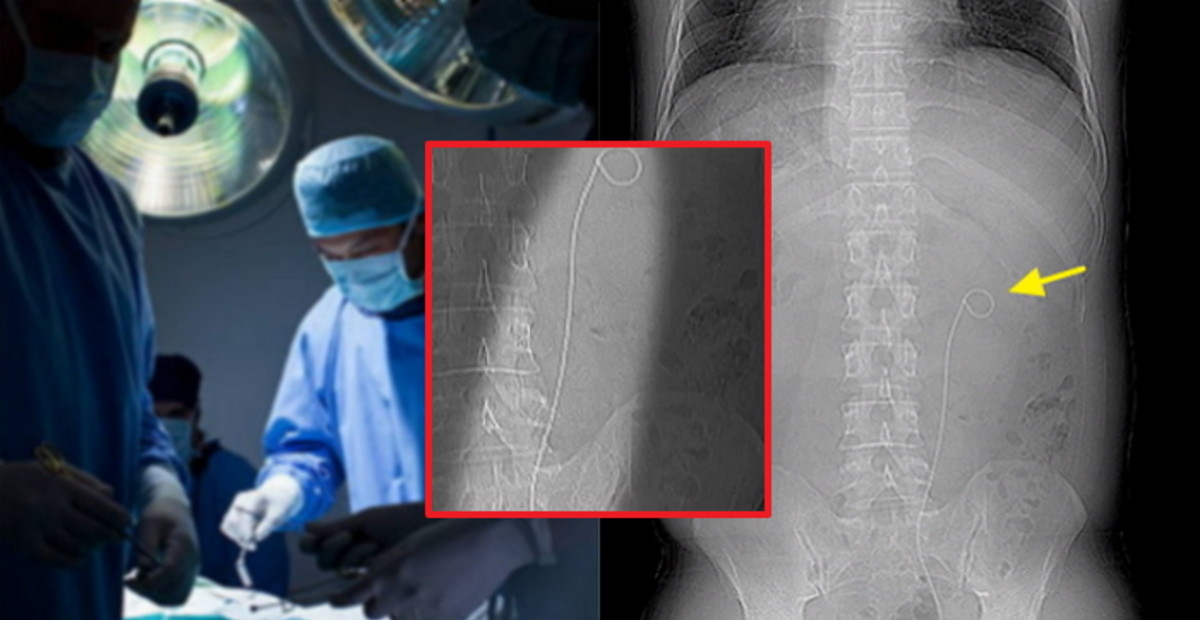

결과는 매우 충격적이었다. 박씨의 뱃속에는 약 3년 9개월 전 받은 수술에서 사용했던 30cm 길이의 철사가 고스란히 남아있었다.

뱃속에서 도구를 빼낸 박씨는 병원을 상대로 항의했으나, 병원은 오히려 박씨에게 책임을 물었다.